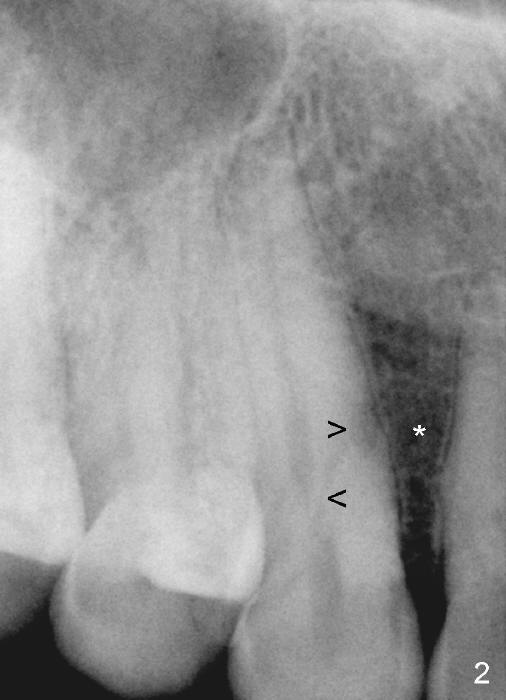

A male patient had trauma to the tooth #6 at the age of 13.  The affected tooth has remained asymptomatic for more than 30 years (Fig.1).   X-ray reveals an oblique root fracture (Fig.2 >) with radiolucency in the mesial alveolus (*, apparently normal trabecular pattern).  Six years later (Feb. 2011), an acute infection develops (Fig.4 *).  It requires incision & draining and antibiotic.  At that time, the trabecular pattern disappears around the fracture line mesially (Fig.3 *).  Four months later cone beam CT shows bone loss between #6 and 7 (Fig.5 *).  Root canal therapy is done as a palliative measure (Fig.6 R; C: Cavit).  Three months later, MTA (mineral trioxide aggregate) is placed in the coronal canal next to the fracture line (Fig.7 M).  It is hoped that MTA can promote nearby bone and cementum to regenerate to seal the fracture line.  Four months after MTA application, there is no sign of bone regeneration (Fig.8).  Bone is lost for approximately 7 mm.